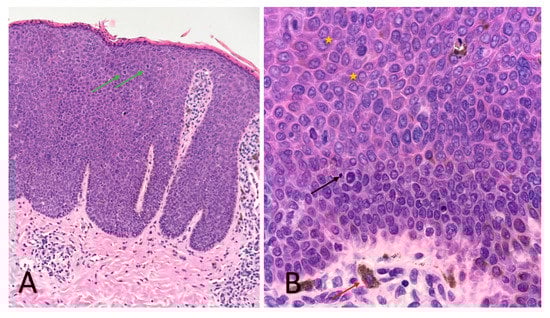

An RCM examination was performed in order to obtain more information regarding these lesions, followed by a skin biopsy from one of the papules to confirm the diagnosis. The RCM exam revealed acanthosis, alteration of the honeycomb pattern, with the presence of multiple irregular bright cells in the dermal papillae corresponding to melanophages. The histopathology (Figure 2) exam revealed atypical keratinocytes throughout the entire thickness of the epithelium with increased mitotic activity, suprabasal mitoses, bowenoid nuclear atypia and focal melanic pigmentation with melanophages and dilated blood vessels present in the papillary dermis. The HPV genotyping exam was also performed but with negative results.

Figure 2. Histological aspects of the lesions of BP (haematoxylin-eosin stain): acanthosis with parakeratosis and lymphocytic infiltrate, with the preservation of the integrity of the basement membrane ((A) ×4); pleomorphic keratinocytes with atypia in the entire thickness of the epidermis (yellow star), with mitoses in the upper epidermis (green arrows), apoptotic cells with small pyknotic nuclei (black arrow) and melanophages (red arrow) ((B) ×40).

Although clinically and prognostically different, the histopathological examination of BP highlights changes similar to Bowen’s disease: acanthosis with elongation of rete ridges, multiple mitoses, hyperchromatic nuclei, pleomorphic keratinocytes, multinucleated giant cells, and koilocytes, throughout the superior part of the epidermis, sometimes with perinuclear vacuolisation, without invasion of the basal membrane. Sometimes, the melanic pigment in increased quantity can be observed at the level of the lesions [12]. Pigmented lesions contain keratinocytes with increased melanin and melanophages in the upper dermis. In the superficial dermis, dilated and tortuous capillaries and perivascular inflammatory infiltrates of lymphocytes, plasmocytes, and histiocytes can be distinguished [13]. Differentiation from condyloma acuminatum is made by the presence of atypia and numerous mitoses up to the upper third of the epidermis, and in addition to Bowen’s disease, by the presence of koilocytes [2,13].

The correlation of RCM findings with those encountered in the histopathological examination (Figure 2) allows us to follow in real-time the evolution of the lesions under treatment, as well as the potential transformation into SCC, without the need for additional biopsies. In addition, these correlations allow the clinician to establish the appropriate moment to stop the topical treatment, in which the benefits-risk ratio is highest, and the inflammatory process initiated by the imiquimod is still efficient in clearing the atypical cells.